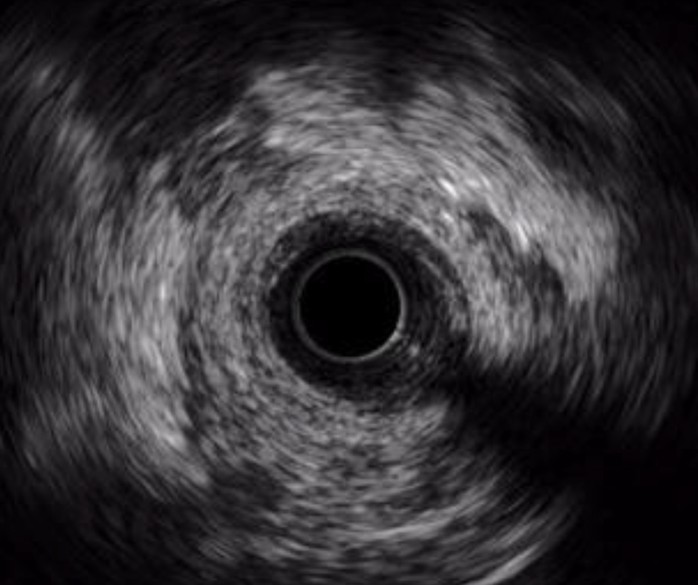

Eagle Eye Platinum 20 MHz

Catéter de imágenes Philips Volcano Eagle Eye Platinum de 20 MHz

Resolución axial: <170 µm

Revolution 45 MHz

Catéter de imágenes Philips Volcano Revolution 45MHz

Resolución axial: 50 µm